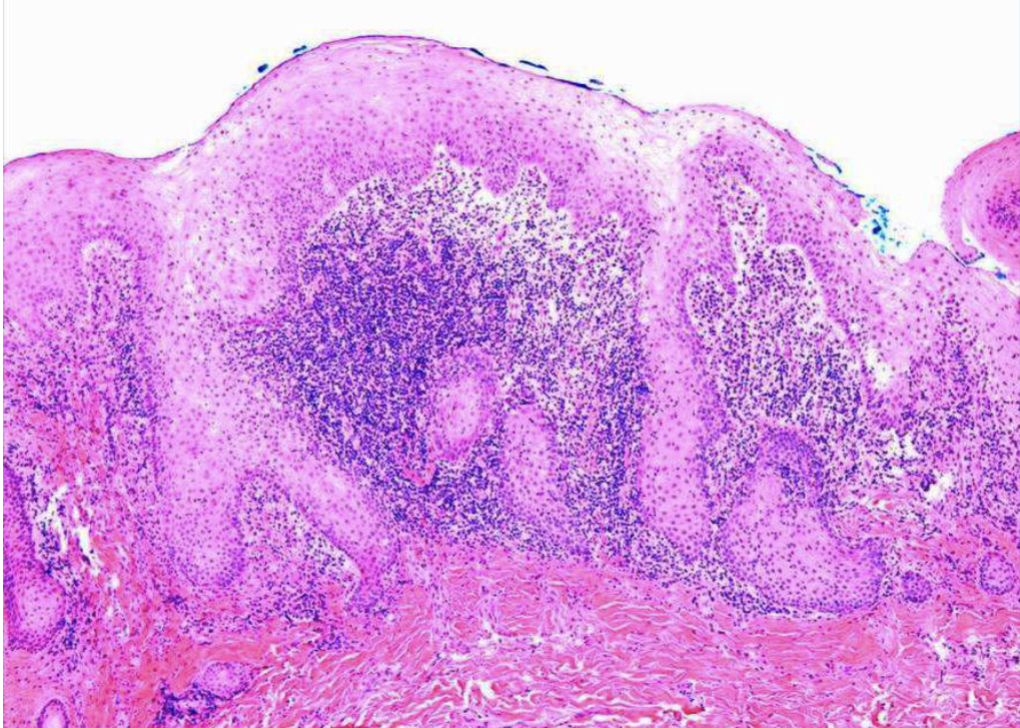

what is this

verruciform xanthoma